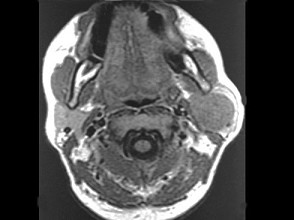

女性,30歲,右側(cè)腮腺無(wú)痛性包塊5個(gè)月,無(wú)面癱,觸診腫塊質(zhì)韌,表面光滑。大小約6×8厘米,B超示腮腺淺葉實(shí)性腫塊 ,均質(zhì),包膜完整。患者相片及影像資料見(jiàn)下圖。

8.患者應(yīng)該診斷為  (    )

9.患者的最佳手術(shù)方式是  (    )

10.手術(shù)中若以下頜緣支尋找面神經(jīng)主干,其主要標(biāo)志是  (    )

正確答案:8.B;9.B;10.A